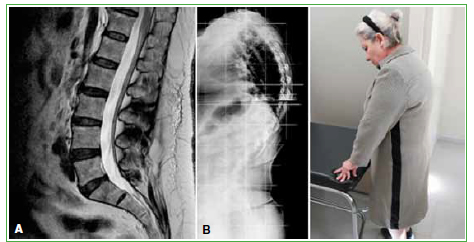

Figura 5.

Paciente de la Figura 4. A. Resonancia magnética que muestra una columna sana sin patología estructural. B. Radiografía que revela cifosis y lordosis marcadas en bipedestación por debilidad muscular. Se realizó resonancia magnética muscular de cuerpo entero. La atrofia resultó ser selectiva de la musculatura erectora lumbar.